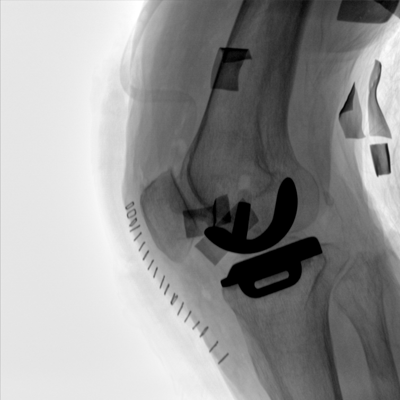

動(dòng)態(tài)板C形臂 開(kāi)啟清晰影像新篇章 PLX118F

臨床適用科室:骨科、普通外科、矯形外科、創(chuàng)傷外科、泌尿外科、脊柱外科、疼痛外科、消化科、婦科等科室。

大尺寸動(dòng)態(tài)平板探測(cè)器,高DQE、低噪聲、圖像清晰。采用多分辨率圖像增強(qiáng)處理技術(shù),不同部位不同圖像處理算法,滿足客戶多樣化的需求。